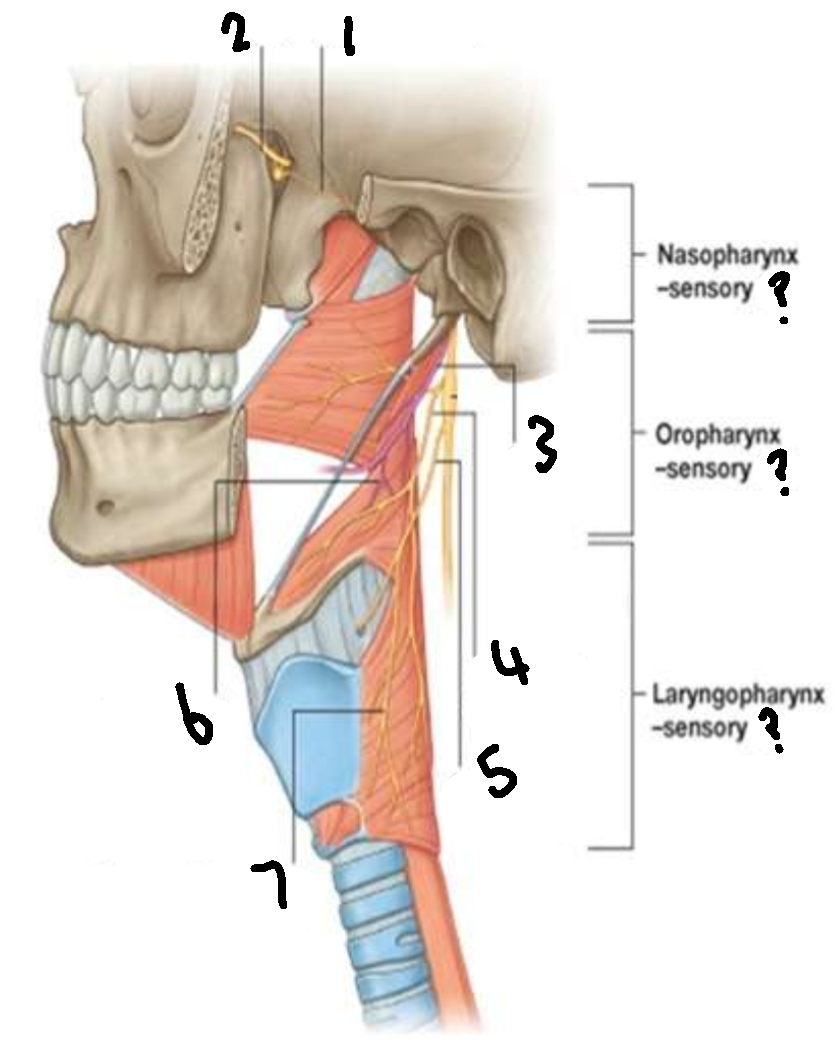

What provides sensory innervation to the nasopharynx?

mandibular branch of trigeminal V2

What provides sensory innervation to the oropharynx?

glossopharyngeal IX

What provides sensory innervation to the laryngopharynx?

vagus X

What is 1?

pharyngeal branch of V2

What is 2?

maxillary branch of trigeminal V2

What is 3?

glossopharyngeal IX

What is 4?

pharyngeal branch of vagus X

What is 5?

superior laryngeal nerve

What is 6?

pharyngeal branch of IX

What is 7?

external laryngeal branch of superior laryngeal nerve of X